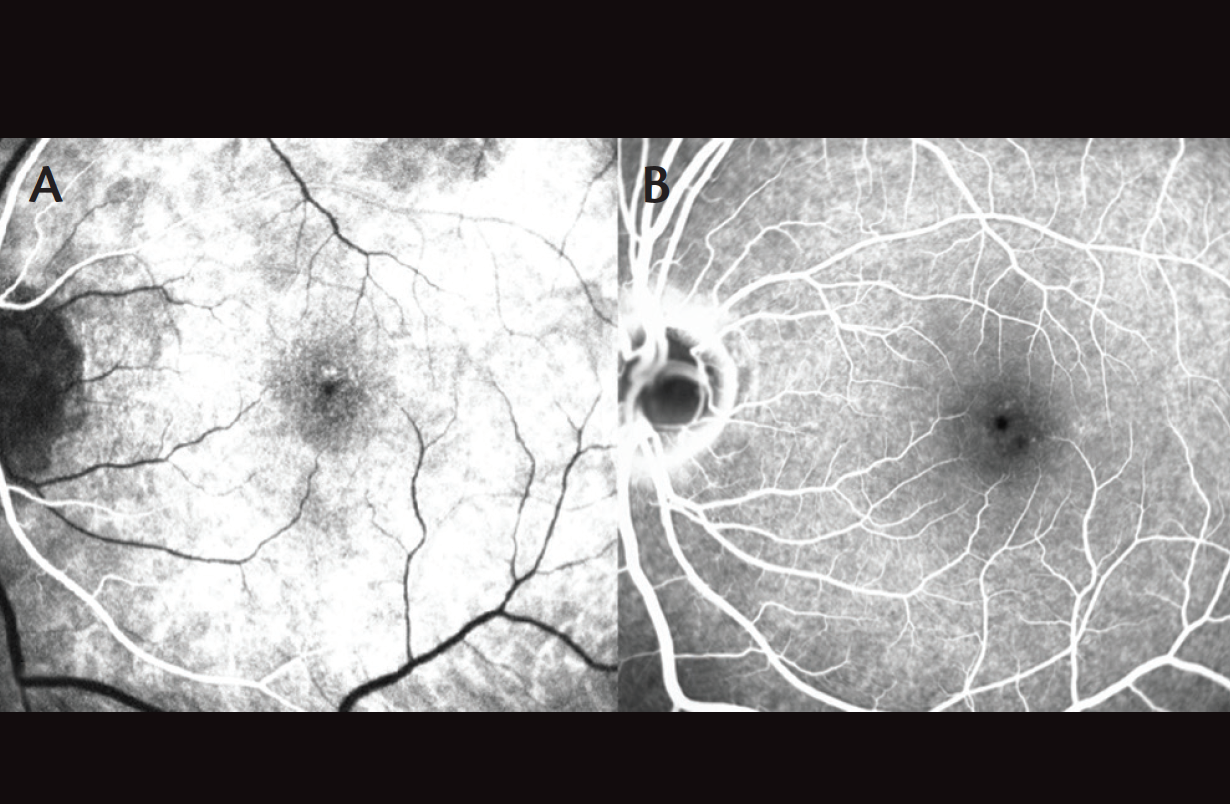

Baseline visual acuity before this presentation was 20/25 in each eye (OU). At this visit, her visual acuity OS had decreased to 20/400. Anterior segment examination was notable for an absence of inflammation. Funduscopic exam OD revealed focal hypopigmentation at the fovea (Figure 2A), and spectral-domain optical coherence tomography (OCT) demonstrated a focal defect involving the outer retina and ellipsoid layer, which was stable from 3 years prior (Figure 3). Fundoscopic exam OS was notable for absence of any posterior segment inflammation and a circumscribed central granular yellow lesion (Figure 2B). OCT revealed disruption of the subfoveal ellipsoid layer, hyperreflective debris involving the outer retina and apical surface of the retinal pigment epithelium (RPE), and a thickened choroid OS (Figure 4). Fluorescein angiography (FA) OS demonstrated early central hypofluorescence and parafoveal patchy hyperfluorescence without leakage (Figure 5). Electroretinography (ERG) demonstrated normal amplitudes OD and reduction of macular sensitivity OS.

Figure 5. Early (A) and late (B) FA images OS demonstrate early central hypofluorescence with parafoveal patchy hyperfluorescence without leakage.